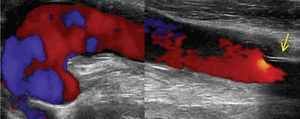

Objectivamente apresentava volumosa massa pulsátil e expansível indolor infra-clavicular esquerda, com enxerto pulsátil e pulsos distais presentes no membro inferior esquerdo. A avaliação por «Triplex Scan» e angioTC mostraram disrupção completa da anastomose axilar e migração distal da prótese axilo-femoral permeável (figs. 1 e 2).